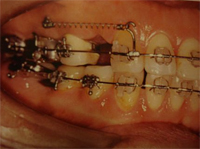

A técnica de inserção dos mini-implantes ortodônticos é bastante simples. Sob anestesia local, seleciona-se o local de seleção dos implantes, geralmente entre as raízes dos dentes envolvidos, tanto na mandíbula, mas especialmente na maxila. Faz-se pequena incisão no local e insere-se o mini-implante, manualmente ou com uso de brocas. Quase sempre não são necessárias suturas, já que a incisão é mínima e a recuperação é indolor e rápida (figura 3).

3.Mini implante em posição